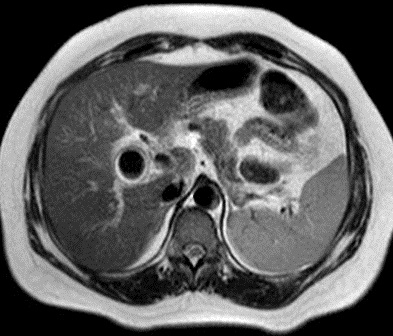

Image IRM : C'est image hypersignal de

vesicule biliaire dilate sur T2 avec grand calcul

hypointense a infundibulum . Image de compress du calcul sur

canal hepatique commune . Image de dilatation de voie

biliaitre hyperintense intrahepatique peut se en voyait sur

T2

Syndrome de Mirizzi : Image

distendue vesicule biliaire a isointense avec

epaississement de sa paroi : Image radiologique IRM

en coupe axiale pondere sur T1 |

|

Meme cas en coupe a

travers l'infundibulum de la vesicule biliaire : Une

grand calcul a hyposignal arrondie en coincee

a infudibulum de la vesicuile biliaire ( Image

radiologique IRM en coupe axiale sur T1 ) |

En coupe pondere sur T2 (

l'eau est hypersignal ) on peu en vue la vesicule

biliaire est distendue ,hyperintense tres net

et image de dilatation legere de voie biliaire

intra- hepatique |

Le calcul est en hyposignal

tres grand et arrondie en compressant le canal

hepatique commun . Image radiologique IRM pondere

sur T2 . |

Meme cas en coupe IRM a T2 coronal . La

vesicule biliaire est distendue et hyperintense . Le

calcul est en compessse sur la voie biliaire

principale . Le canal hepatique commun et voie

biliaire en amont est en leregement dilate . |